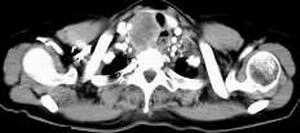

女,61岁,吞咽困难(包括开水)已久。

食道中上段癌并锁骨上窝淋巴结转移.

1、同意食道上段ca併淋巴结转移。

3、右侧甲状腺是否有问题?是否甲状腺ca转移食道上段。因为肿块顶部图像没有,请楼主展示,谢谢!

食道中上段中分化鳞癌伴锁骨上淋巴结转移